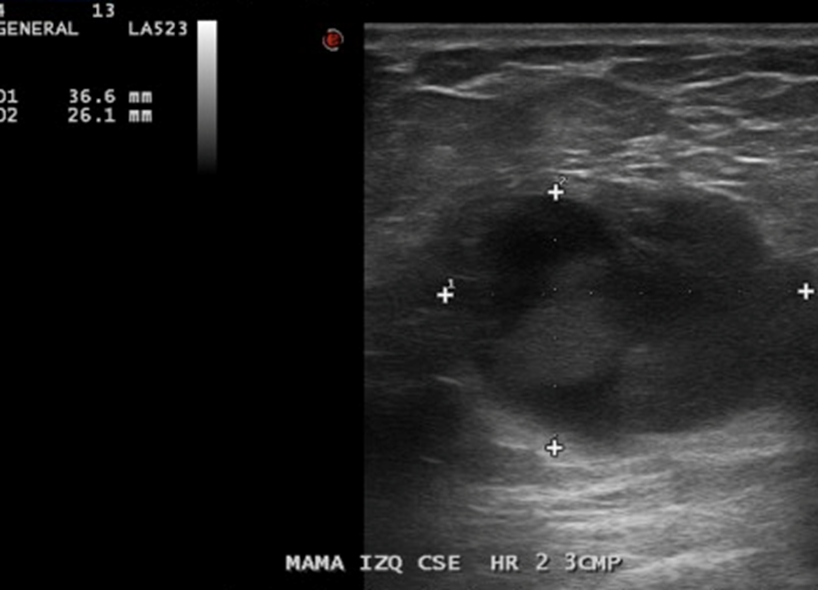

En Mama IZQ CSE HR 2, a 3 CMP, imagen nodular hipoecogénica, ovalada, 31 x 36 x 26 mm.

• La mama izquierda presenta en el cuadrante supero-externo, eje horario 2, a 3 cm. del pezón, imagen nodular hipoecogénica, bien definida, ovalada de 36 x 26 x 31 mm., sugerente de lesión quística con contenido, no vascularizado. Esta lesión presenta escaso refuerzo acústico posterior.

Impresión: Lesión sugerente de quiste con contenido en mama izquierda, se recomienda control evolutivo. BIRADS US 3.